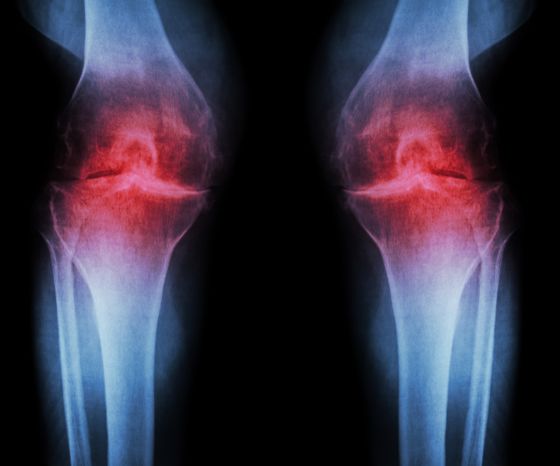

Klasickým znakem osteoartrózy kolenního kloubu jsou histologické změny kvality a tloušťky kloubní chrupavky. Úbytek kloubní chrupavky vede k hypertrofii subchondrální kosti a tvorbě osteofytů na okrajích kloubních ploch. Dalším důsledkem je chronický zánět synoviální tkáně. Všechny tyto změny vedou k nepravidelnému povrchu kloubů, kostnímu zvětšení, možnému zesílení kloubního pouzdra a nakonec k hydropsu. Výsledné zmenšení kloubního prostoru je patrné na rentgenových snímcích, proto se také hovoří o "radiologické osteoartróze".

Nejčastěji používaným klasifikačním systémem pro radiologickou osteoartrózu je stupnice Kellgrena a Lawrence(Kohn et al. 2016):

- Stupeň 0: nejsou přítomny žádné radiografické znaky OA.

- Stupeň 1: pochybné zúžení kloubního prostoru a možné osteofytické vyklenutí.

- Stupeň 2: definitivní osteofyty a možné zúžení kloubního prostoru na předozadním snímku při zatížení.

- Stupeň 3: mnohočetné osteofyty, určité zúžení kloubního prostoru, skleróza, možná kostní deformita.

- Stupeň 4: velké osteofyty, výrazné zúžení kloubního prostoru, těžká skleróza a určitá kostní deformita.